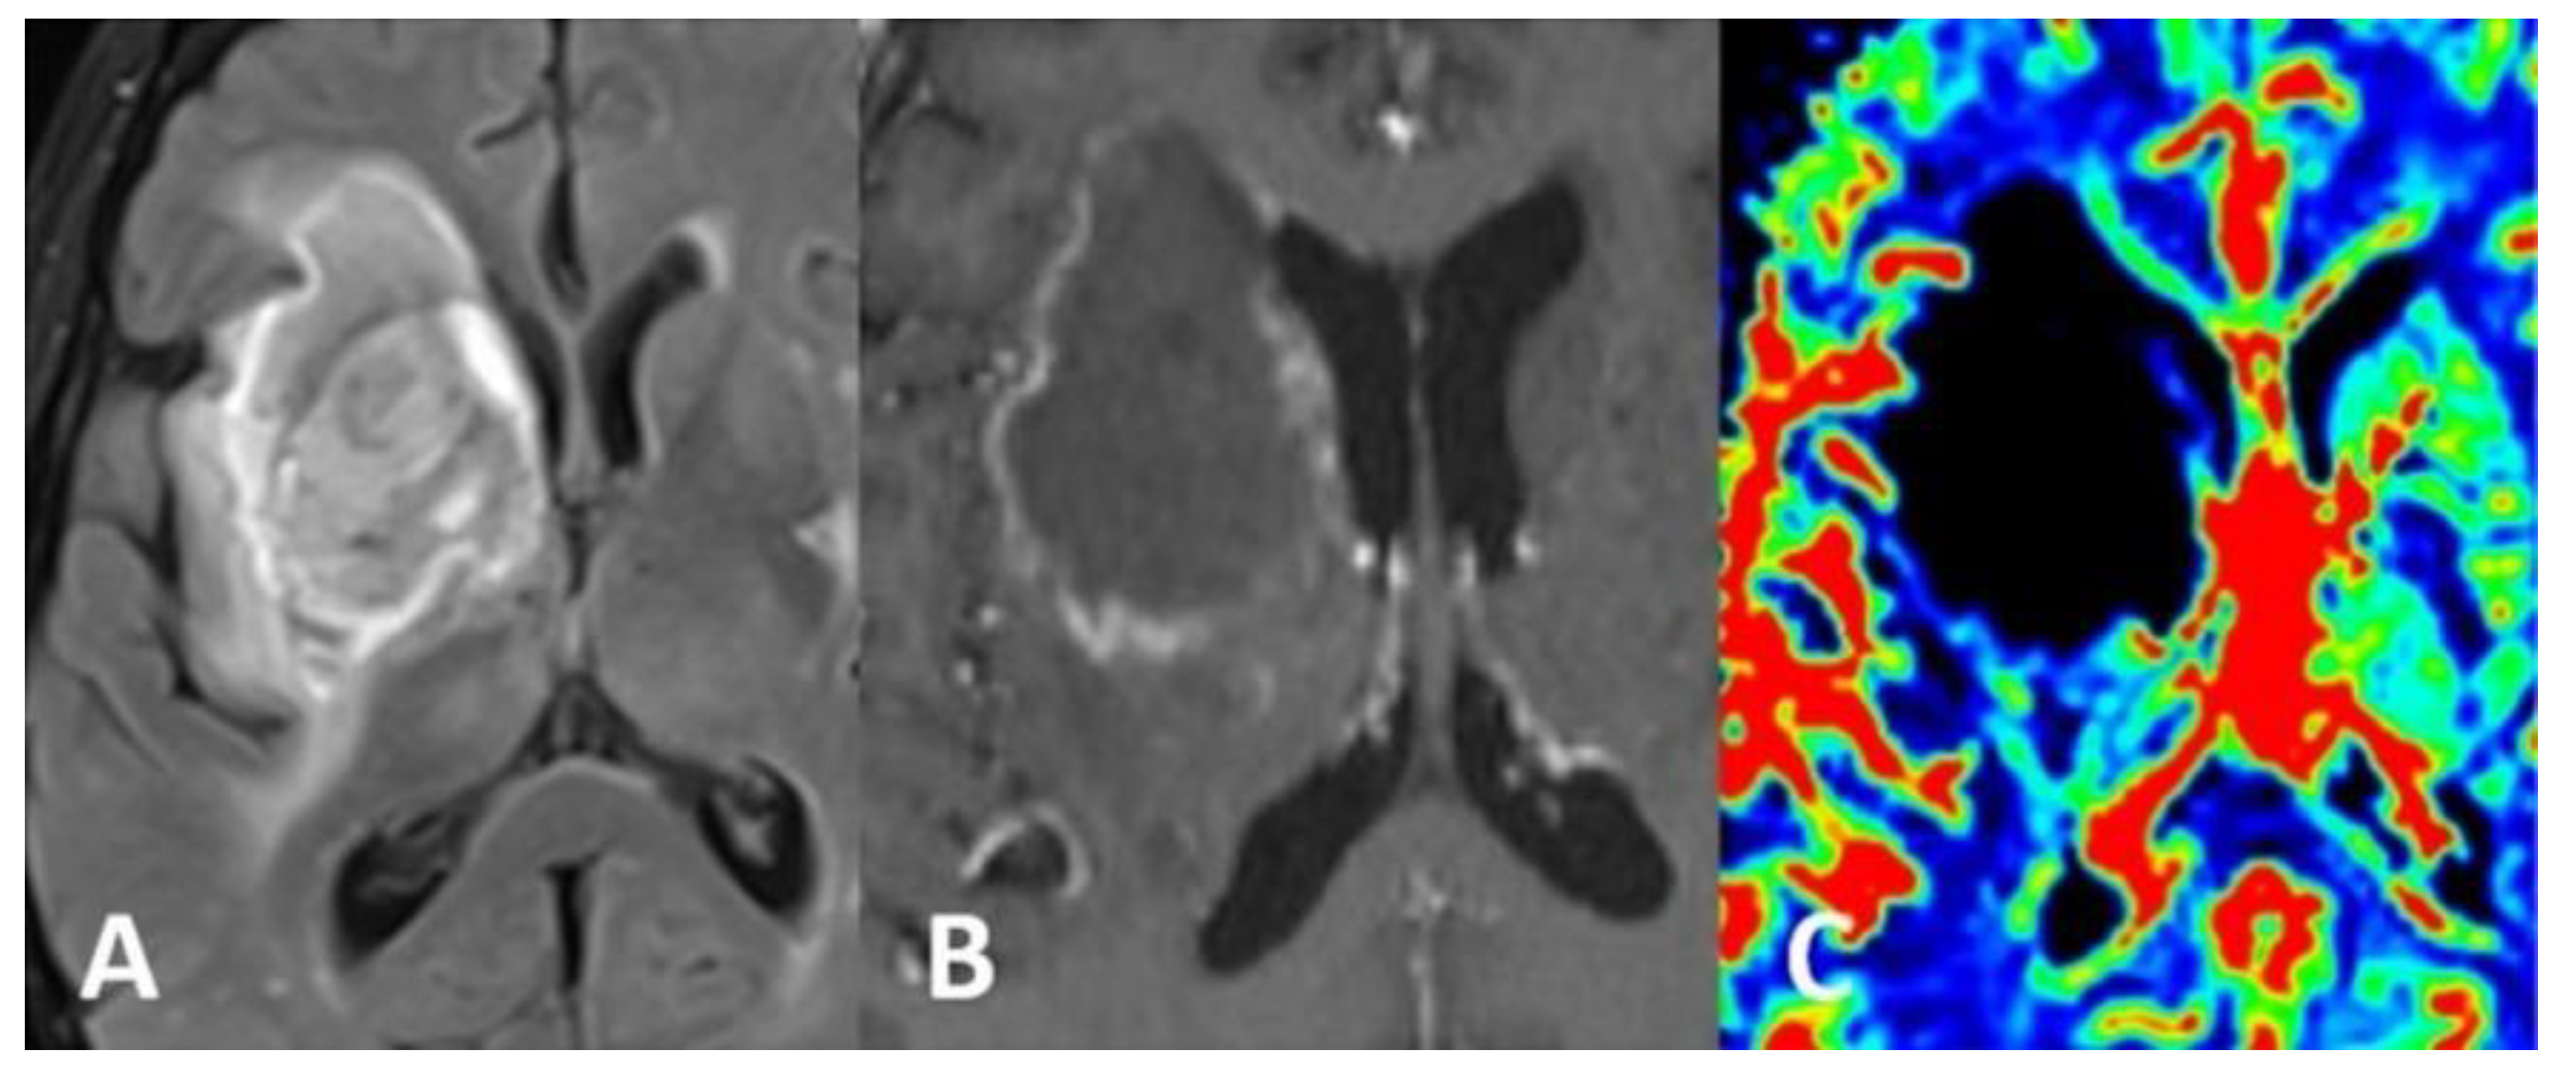

Computed tomography (CT) scan of the brain revealed the presence of a focal space-occupying hypodense lesion in the right basal ganglia, surrounded by edema. The lesion caused mass effect with effacement of ipsilateral cerebral sulci, buckling of the ventricular system (without hydrocephalus) and mild deviation of midline structures to the left (Figure 1). On magnetic resonance imaging (MRI), the lesion was relatively heterogeneous on T2/FLAIR and exhibited marginal enhancement following gadolinium injection. Perfusion-weighted imaging demonstrated significant decrease of cerebral blood flow (CBV) within the lesion (Figure 2). Following imaging characterization of the lesion, an intraoperative consultation with brain biopsy was performed through a right parietal burr hole. A brain smear revealed the presence of brain tissue with abundant dirty necrosis and predominantly acute inflammatory cells. Cystic structures containing encapsulated microorganisms were also identified, raising the hypothesis of TG infection. A brain biopsy was later performed and revealed not only cysts containing bradyzoites but also free microorganisms (tachyzoites) across the sample. Immunohistochemical staining with antibodies against TG confirmed the diagnosis of cerebral toxoplasmosis, highlighting the free tachyzoites (Figure 3). A post-biopsy CT scan excluded procedure-related complications.

Figure 1.

CT scan of the brain (A,B) showed a space-occupying hypodense lesion in the right basal ganglia, surrounded by edema involving the frontal and temporal lobes. Mass effect was seen with effacement of cerebral sulci, compression of the ventricular system and mild left deviation of midline structures.